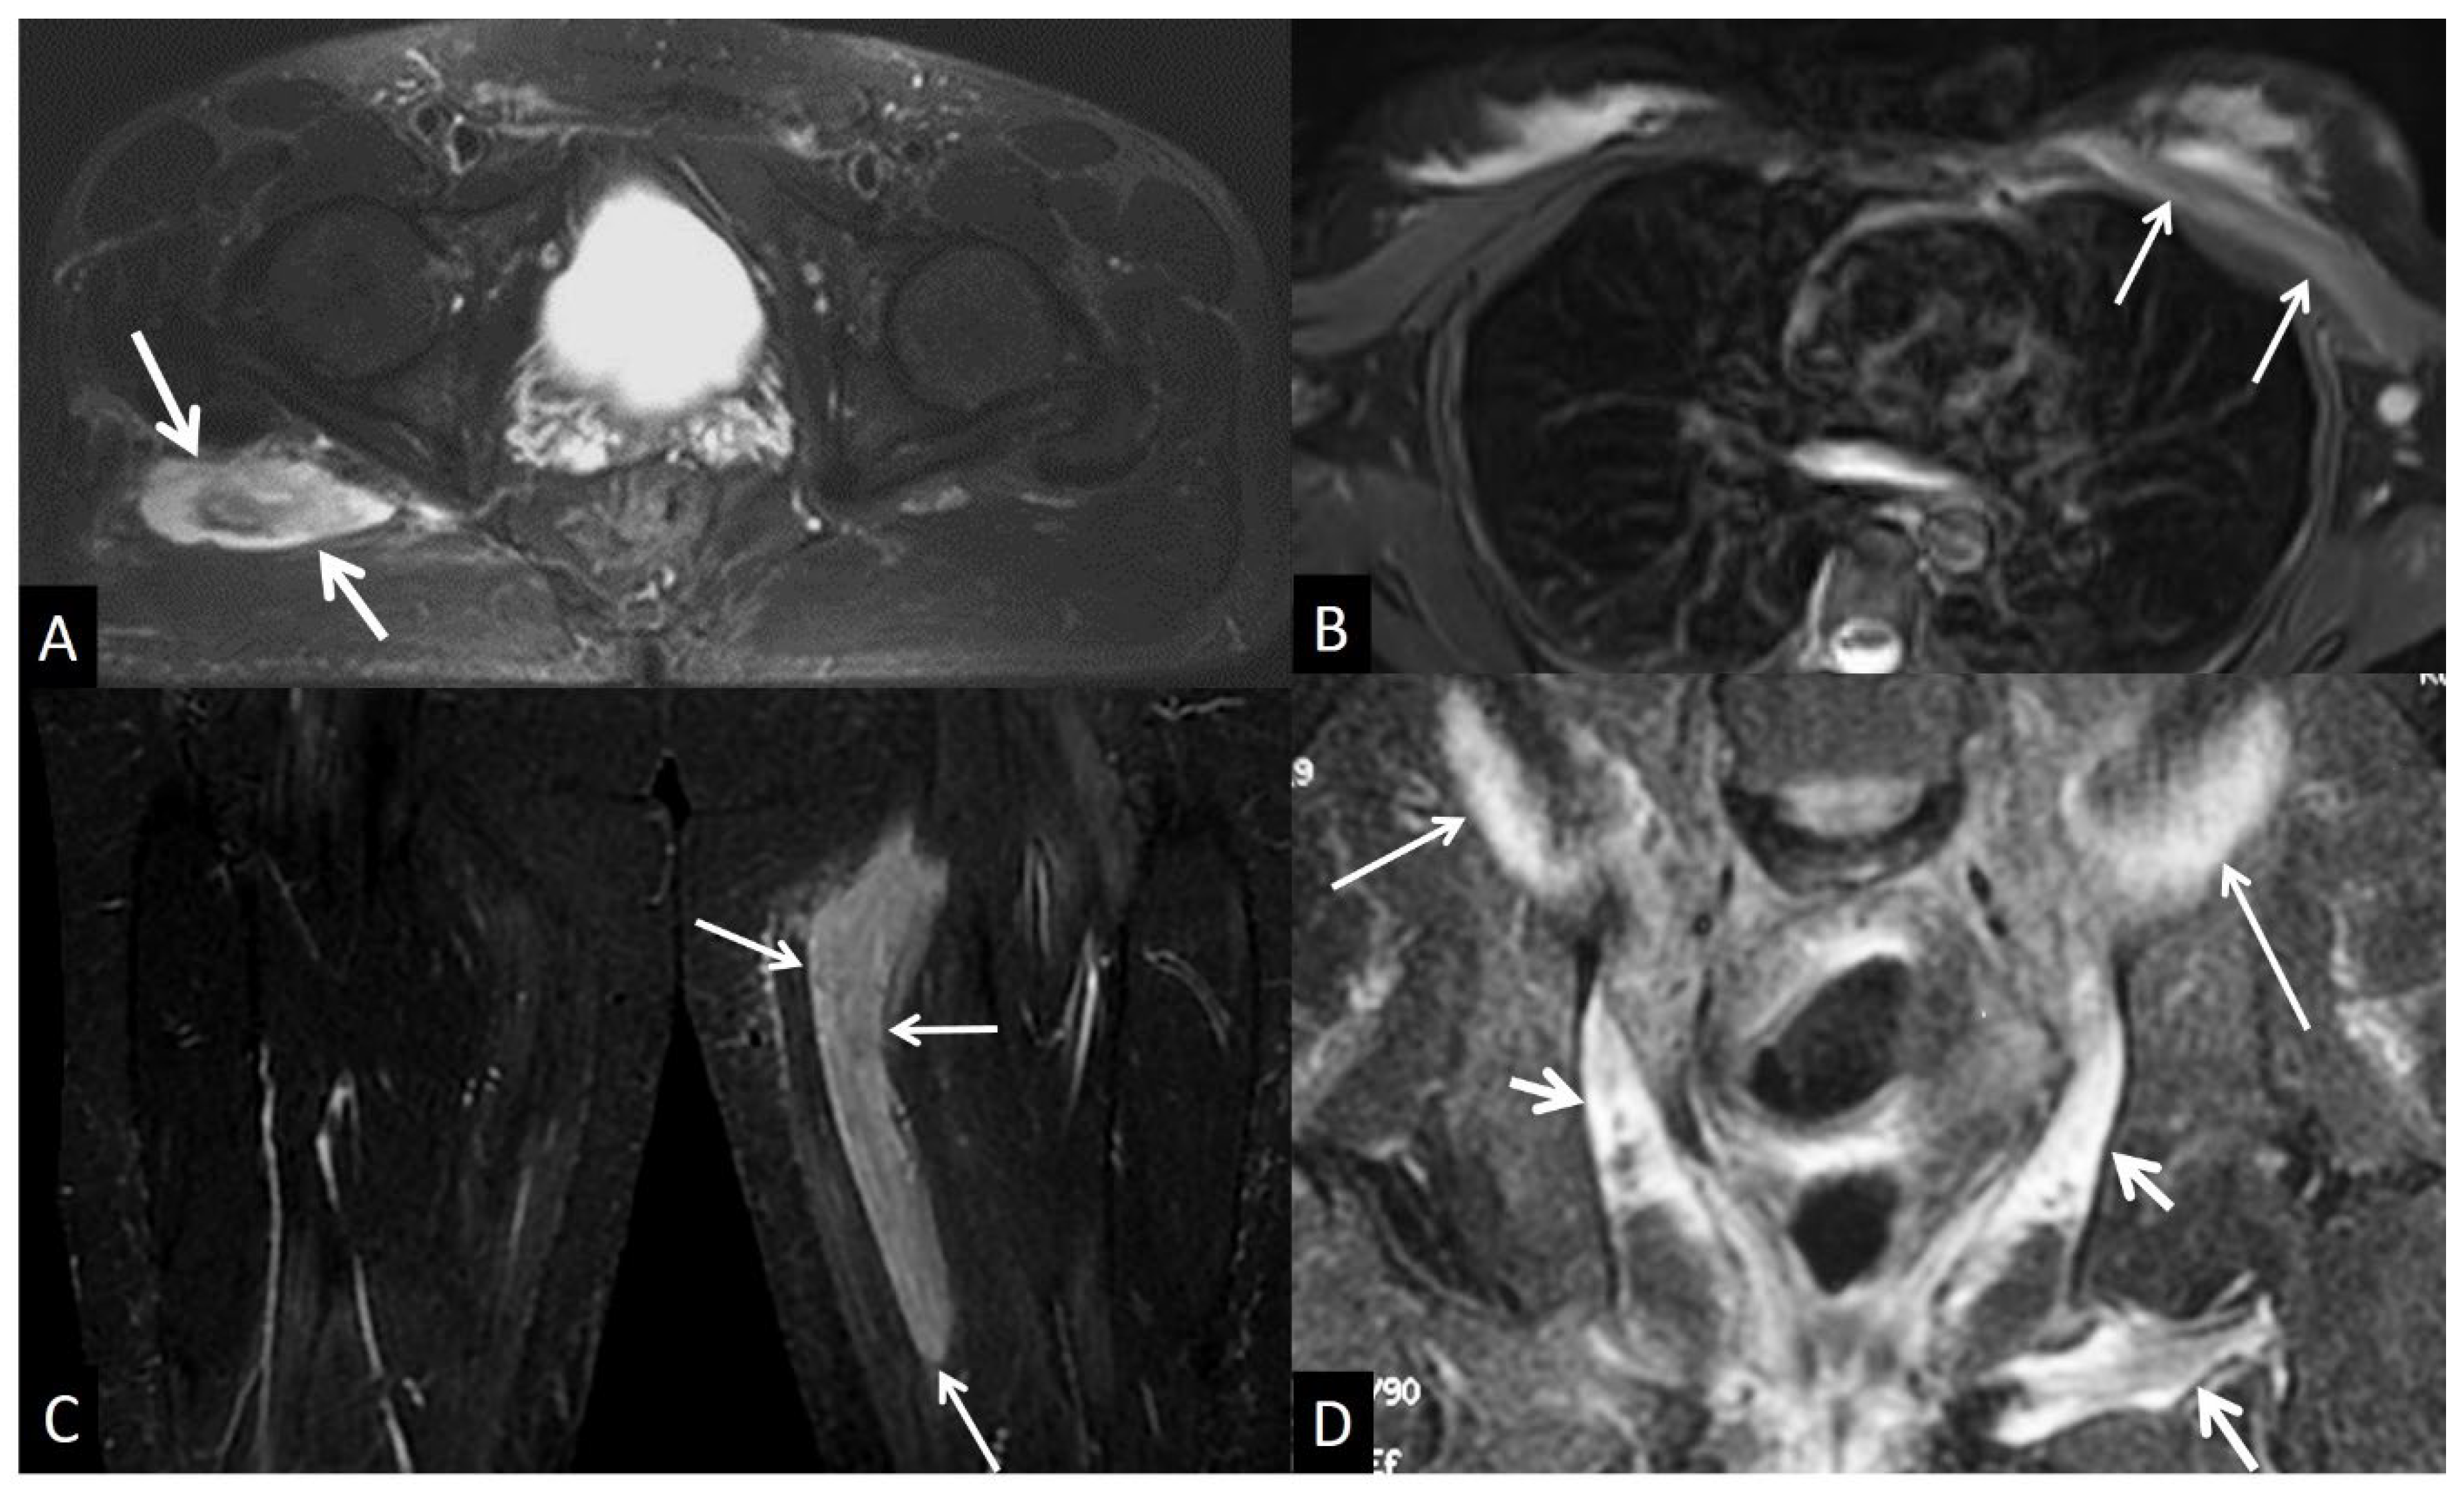

4. Muscles and Soft Tissues

4. a. Non - Infectious Subcutaneous Edema

4. b. Non - Infectious Fsciitis

4. b.i. Eosinophilic Fasciitis

4. b.ii. Paraneoplastic Fasciitis

4. b.iii. Nodular Fasciitis

4. b. Inflammatory Myopathies

4. c. Muscle Denervation

4. d. Traumatic Soft Tissue Injury

4. d.i. Muscle Contusion

4. d.ii. Muscle Strain

4. d.iii. Delayed Onset Muscle Soreness

4. d.iv. Rhabdomyolysis

4. d.v. Myositis Ossificans

4. e. Neoplasm and Post Therapy Soft-Tissue Changes